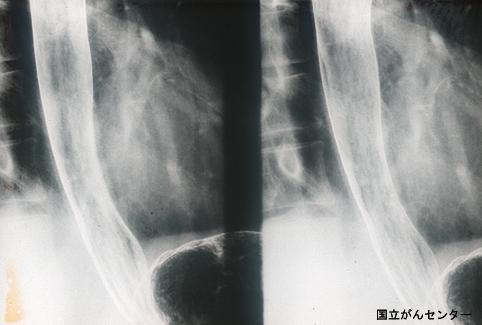

疾患(病理主体)の分類悪性上皮性腫瘍/扁平上皮癌

部位(臓器別)食道/下

検査方法X-P

腫瘍の肉眼分類0型(表在型)/IIc型(IIc)

病変の最大径(ミリ)10〜14

腫瘍の深達度mm

多発腫瘍(同一臓器)有(同時性)